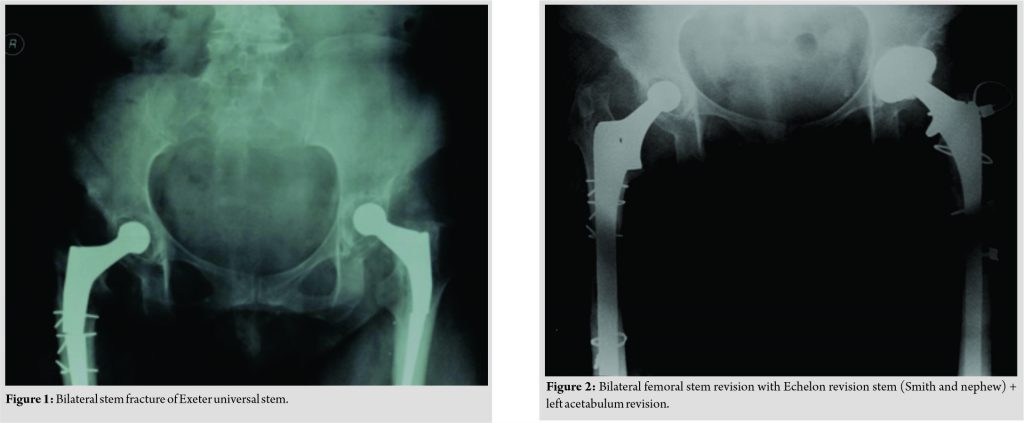

Seventeenyears ago, a45-year-old lady was admitted to our hospital due to coxarthrosis secondary to developmental hip dysplasia. In six months interval, she underwent bilateral THA with Exeter™ Universal Hip system. She had re-operated on her 3rd year because of right femoral stem fracture.Since then, she has beenexamined at the outpatient clinic regularly on1-year-based intervals. Onher last follow-up, the physical examination revealed minimal pain on her right thigh and nothing more. The patient was 1.62 m tall and weighed 84 kg, with abody mass index (BMI) of 31.25kg/m2 (obese class).There was no difference between the range of motion of bilateral knees and hips when compared withprevious records. The patient’s gait was observed adequately, and nothing significant was detected. There was no trauma or obvious activity experienced. Radiographs of the pelvis and bilateral femur were obtained,and it was demonstrated that both femoral stems were broken (Fig. 1). It was also revealed that radiolucent lines had seen both femoral stems and left acetabulum.The patient was informed of the fact that this asymptomatic situation requires revision surgery. With the informed consent of the patient, revision surgery was scheduled. Both thefractured stems were removed by extended femoral osteotomy via a lateral approach.Intraoperative examination revealed that the right acetabular component was well-fixed but there was a loosening of the left acetabularcomponent.Acetabularrevision was performed to the left side. Echelon cementless revision hip system (Smith and Nephew) was used for the right and left sides (Fig. 2). Patient was stood–up on the first post-operative day and weight – bearing was permitted as much as tolerated. . At the end of 6 weeks, full weight bearing was permitted. She returned to her routine daily life activities after 4 months. The preoperative Harris score was 90.25, and the postoperative Harris score was 91.25. After 2-year follow-up, no major or minor complications were reported.

The basic body structure of Exeter (Stryker, Newbury,UK) has been cemented, collarless, and double tapered since 1970 [2]. The original stems were made up of ductile and relatively low-fatigue-strength alloy EN58. Those are highly polished double-tapered stemsunk within the cement mantle by 1 or 2 mm which was allowing load transmission by compression at bone-cement interface. This may lead to decreased shear forces at the bone–cement interface. This positive characteristic preserves the cement cover and leads to a low unsuccessful rate [2]. Initially, the stems had a sharp angle on the superolateral aspect of the neck.Of the original series of polished Exeter stems, nearly 2%of fractured femoral stems were found during a mean follow-up of 13 years [2]. Latter becauseofan awkward biomechanical feature of sharp angle manufacturer replacedit by smooth curve angle. In 1975, stem thickness increased slightly,andthe alloy was alteredinto 316L with the introduction of matt-surfaced stems. Røkkum et al. [3] reported 3 of 27 matt-surfaced stem fractures. Onfollow-up,fracture of this alloy was associated with high patient weight and activity levels.In 1984,femoral stems manufactured more powerful and less ductile by using stainless steel alloy (Orthinox; high nitrogen stainless steel)and returned to polishes from matt ones in 1986 [4,5]. Howmedica introduced universal modular stem in 1988 which we used in our patient. Bolland et al. [6] analyzed fracture of the universal Exeter femoral stem prosthesis (UEFS). Between 1991 and 2008,nearly 80 cases of fracture (neck and stem) had been reported. As far as literature was investigated, our case is the first to reportsimultaneous bilateral fracture of UEFS. According to a report by Bolland et al. [6], some correctable reasons for stem fractures are using undersized stems,varus placements, poor bone cementing, and inadequate impaction bone grafting. The last two may lead to poor proximal medial support often with the presence of a well-fixed distal portion of the stem. It had been shown to cause increased tensile stress in the mid-lateral part of the prosthetic stem. Most of the stem fractures occurred in smaller sizes (35.5–44). 35.5 mm offset stem is the most common fractured implant size among that 80 cases, and this was four times more than any other stem [7]. Design features are also a significant potential etiologyof failure. Historical metallurgical analyses have demonstrated material defects including gas porosity, nonmetallic inclusion, and interdendritic shrinkage which may contribute to fracture etiology. Active and male patients with increased BMIare more prone to fractures [7,8].